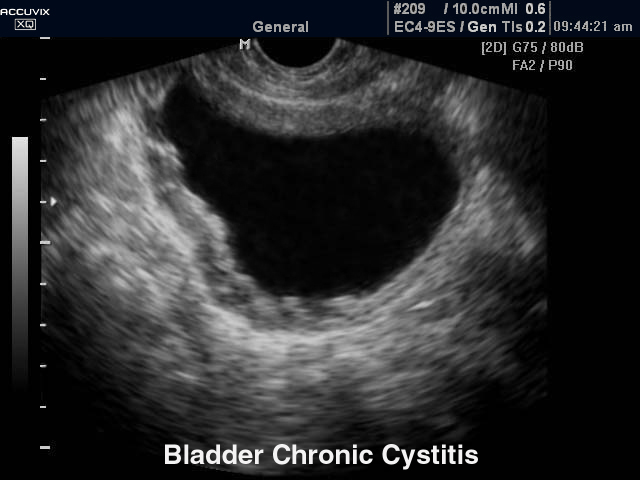

N30.1 Интерстициальный цистит (хронический)

Признаки хронического цистита при УЗИ-диагностике